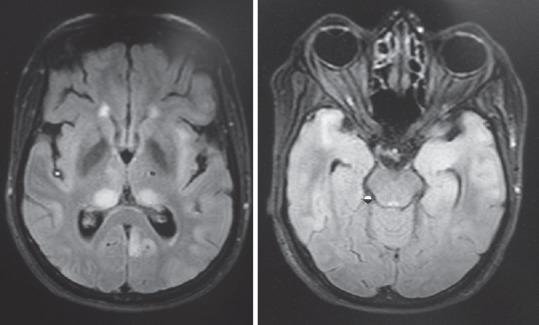

快速进展性认知衰退综合征——我们的经验

Syndromes of Rapidly Progressive Cognitive Decline-Our Experience.

RESULTS AND CONCLUSIONS

Out of 144 patients 42 had immune-mediated encephalopathy, 18 had Creutzfeldt-Jakob disease, 3 had Vitamin B12 deficiency, 63 had infection with neurocysticercosis, 7 had tuberculosis, 2 had HIV, 1 had herpes simplex encephalitis, 1 had neurosyphilis, 1 Whipples disease, 1 had Subacute Sclerosing Panencephalitis, 1 had Mass lesion, 3 had Frontotemporal dementia, and 3 had small vessel disease. Good majority of these patients have infective and immune-mediated causes and less number belong to degenerative group. Therefore, caution is needed to look for treatable cause as it carries a different treatment options and outcome.

结果与结论

144例患者中,42例患有免疫介导性脑病,18例患有克雅氏病,3例患有维生素B12缺乏症,63例患有神经囊尾蚴病感染,7例患有结核病,2例患有艾滋病,1例患有单纯疱疹性脑炎,1例患有神经梅毒,1例患有惠普尔病,1例患有亚急性硬化性全脑炎,1例患有占位性病变,3例患有额颞叶痴呆,3例患有小血管疾病。这些患者中绝大多数有感染性和免疫介导性病因,属于退行性病变组的较少。因此,需要谨慎寻找可治疗的病因,因为其治疗选择和结果不同。